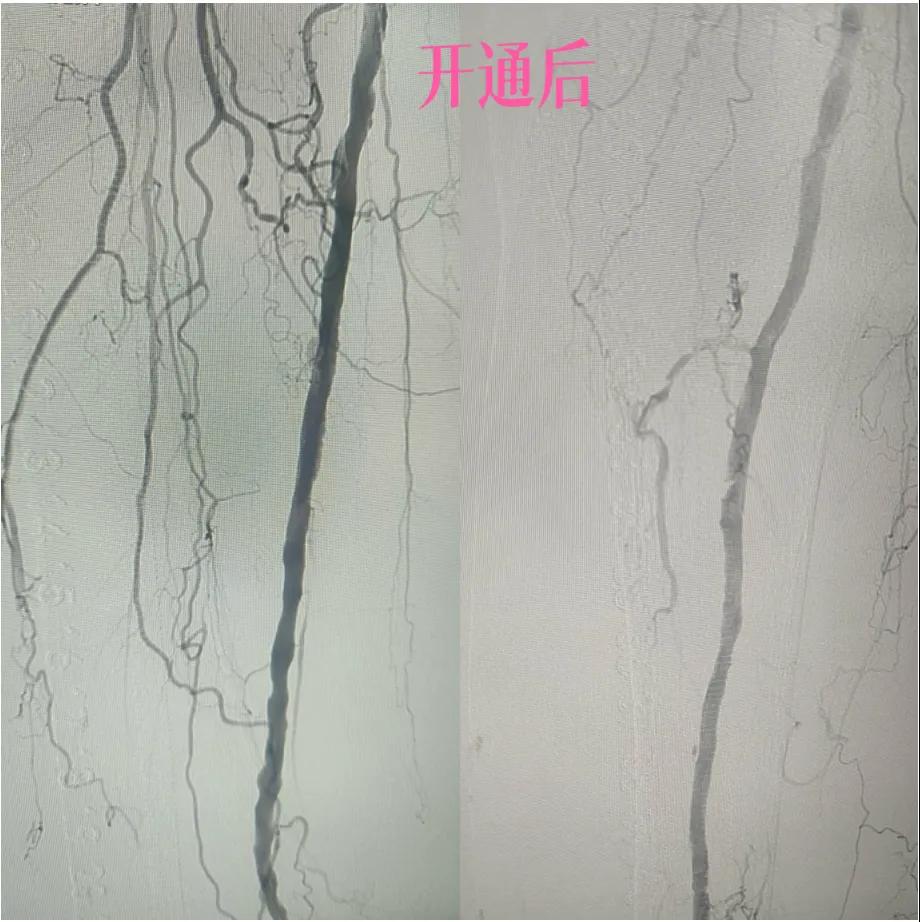

為了挽救患者的患肢,避免截肢,外二科血管外科介入團隊經(jīng)過縝密的術(shù)前討論和評估,決定采用目前微創(chuàng)介入技術(shù)——下肢動脈藥涂球囊擴張成形術(shù)(DCB)。

2.  “探路”與“疏通”:在先進的DSA(數(shù)字減影血管造影)設(shè)備實時引導下,猶如擁有了“透視眼”,導管導絲巧妙穿越病變血管的狹窄、閉塞段。這需要極高的技巧和對血管解剖的深刻理解。

4.  即刻“見證”:再次造影顯示,原本狹窄閉塞的血管段血流恢復(fù)通暢!足部遠端血管顯影較前明顯改善。手術(shù)過程順利,患者靜息痛較前明顯改善。